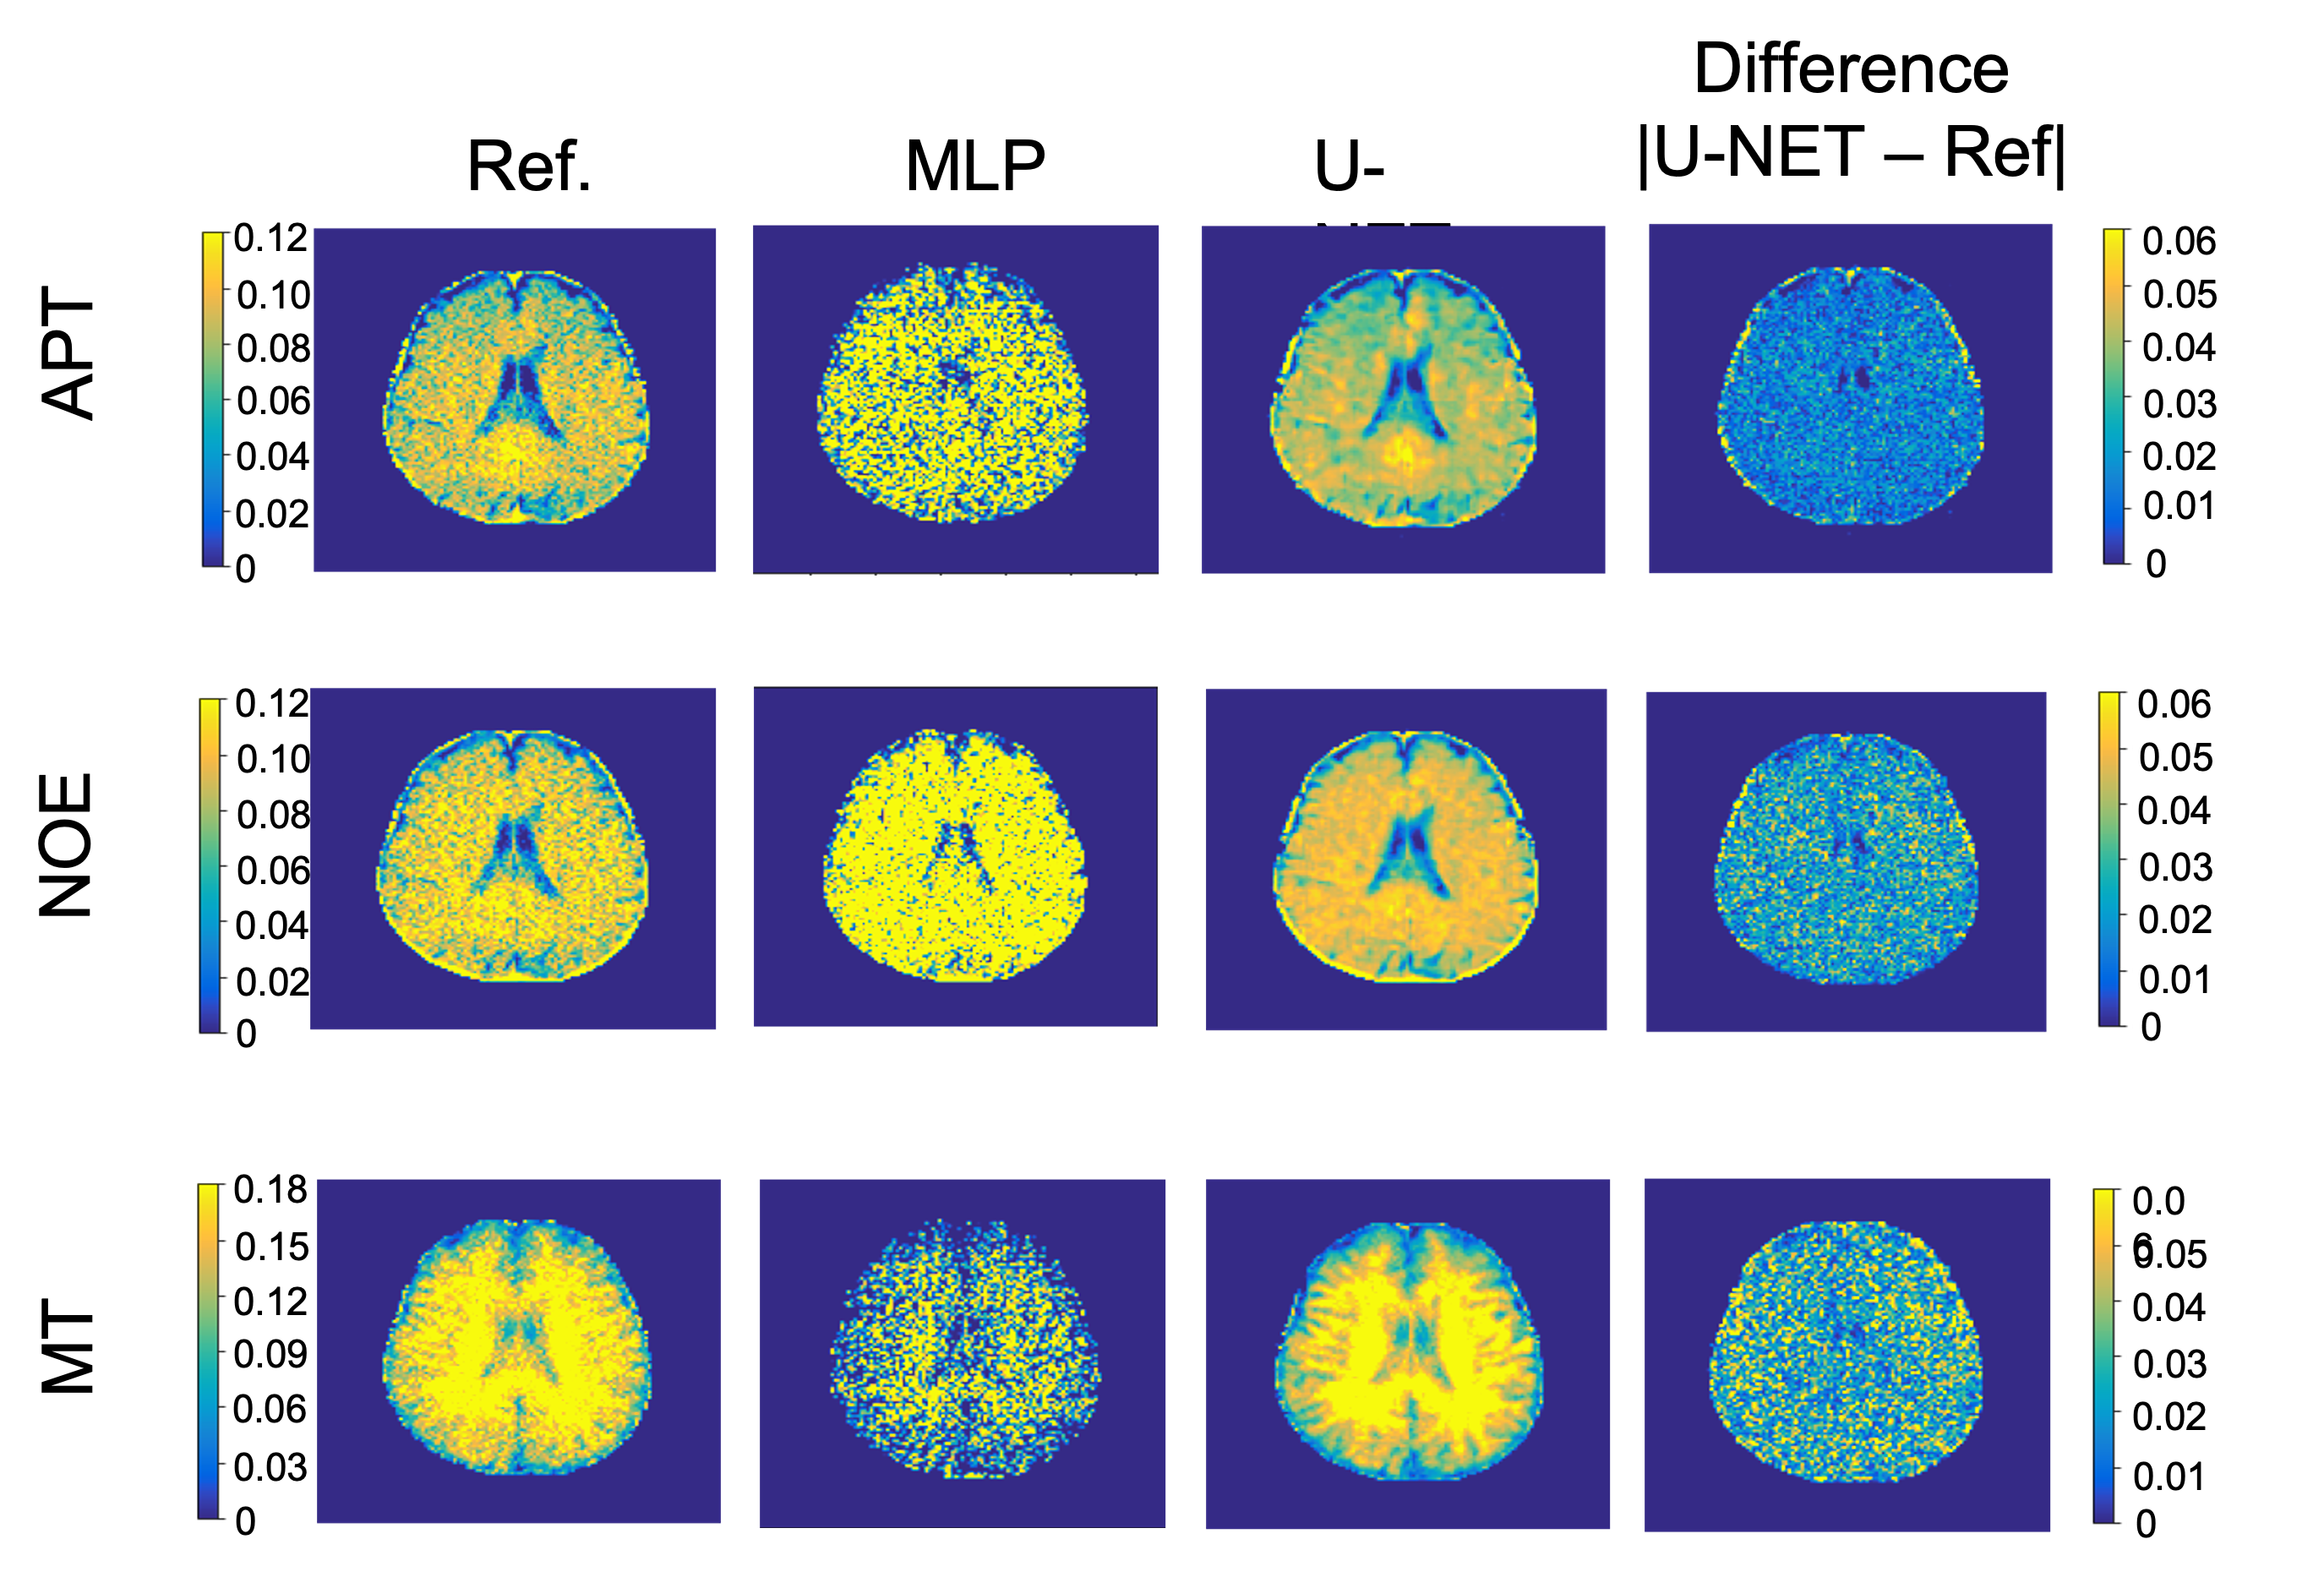

Figure 2 shows representative undersampled CEST maps from the proposed method and from multi-pool fitting. The neural network is able to generate a CEST map (Fig. 2B) more faithful to the fully-sampled reference (Fig. 2A) with less noise. The neural network generates CEST maps with lower mean squared error and higher PSNR than the multi-pool fitting model (Table 2).

Figure 2: CEST maps for 3 different representative slices from the testing dataset. Reference maps were generated using the multi-pool fitting analysis. The undersampled CEST images underwent both multi-pool Lorentzian fitting (MLP) and U-NET inference. Absolute difference maps for the U-NET are shown in the fourth column.